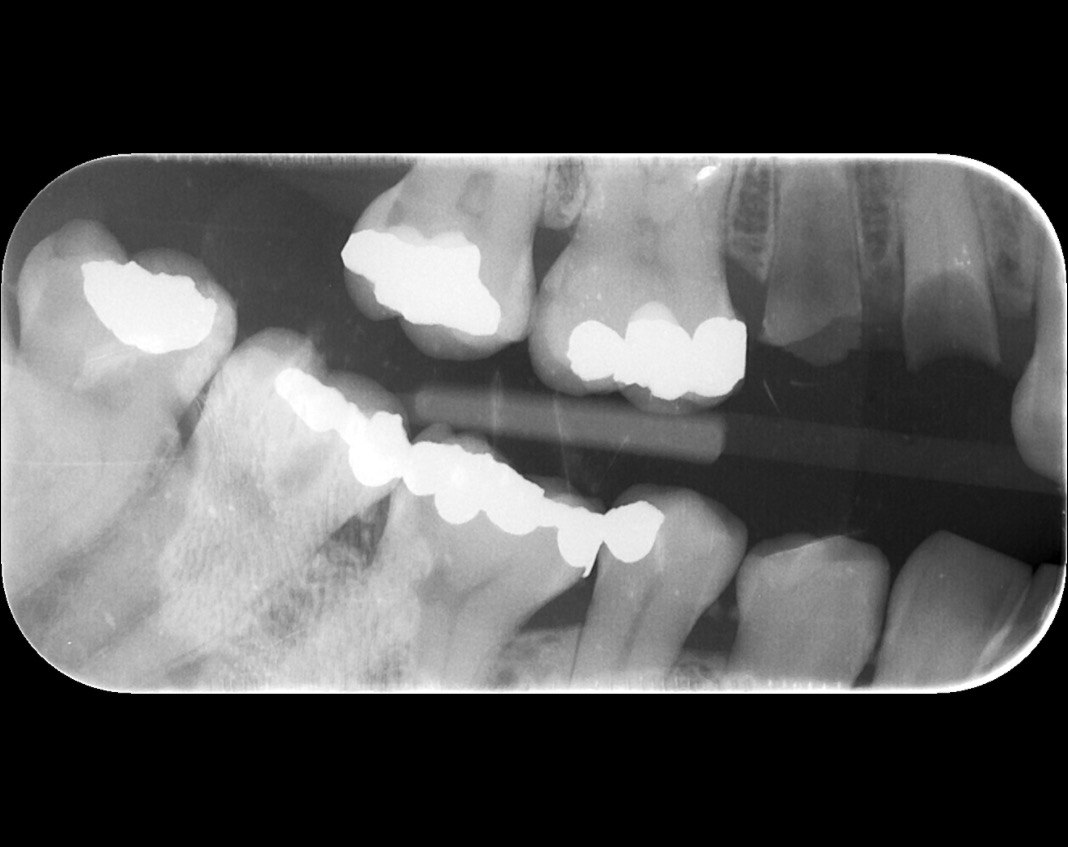

Question 1: What materials cannot be seen in the print of the X ray?

Question2: Which surface shows overhang?

Question 3: Which option is not evident on the print of the X ray?

Question 4: Which options cannot be seen in the print of the X ray?

Question 5: What options cannot be selected for tooth # 4.6?

Question 6: What options cannot be seen in the print of the X ray?

Question 7: What option cannot be identified on the print of the X ray?

Question 8: What condition can be seen in the X ray?

Question 9: Which option cannot be seen in the lower jaw?

Question 10: Which option can be selected for the following X ray?